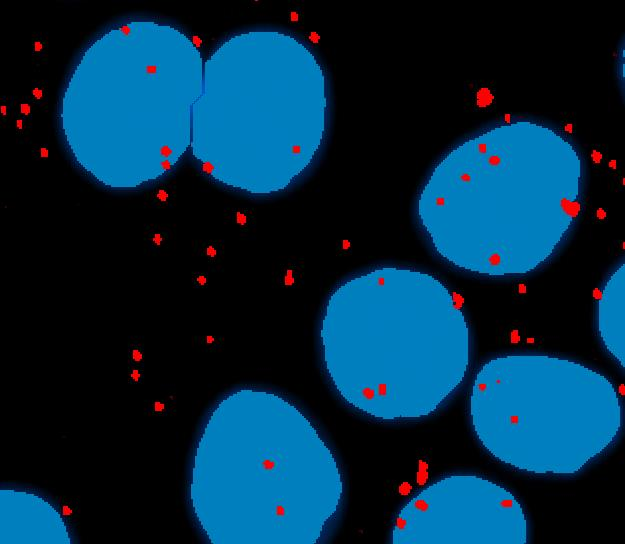

D.微弱光信号的分析(X-ISH) 针对不同的微弱光信号图像,例如FISH ,CISH ,SISH等,可进行基因探针的计数/比率等分析,可针对两种不同的探针信号进行同时分析;

图5 CISH检测(红、蓝色区域可同时检测)